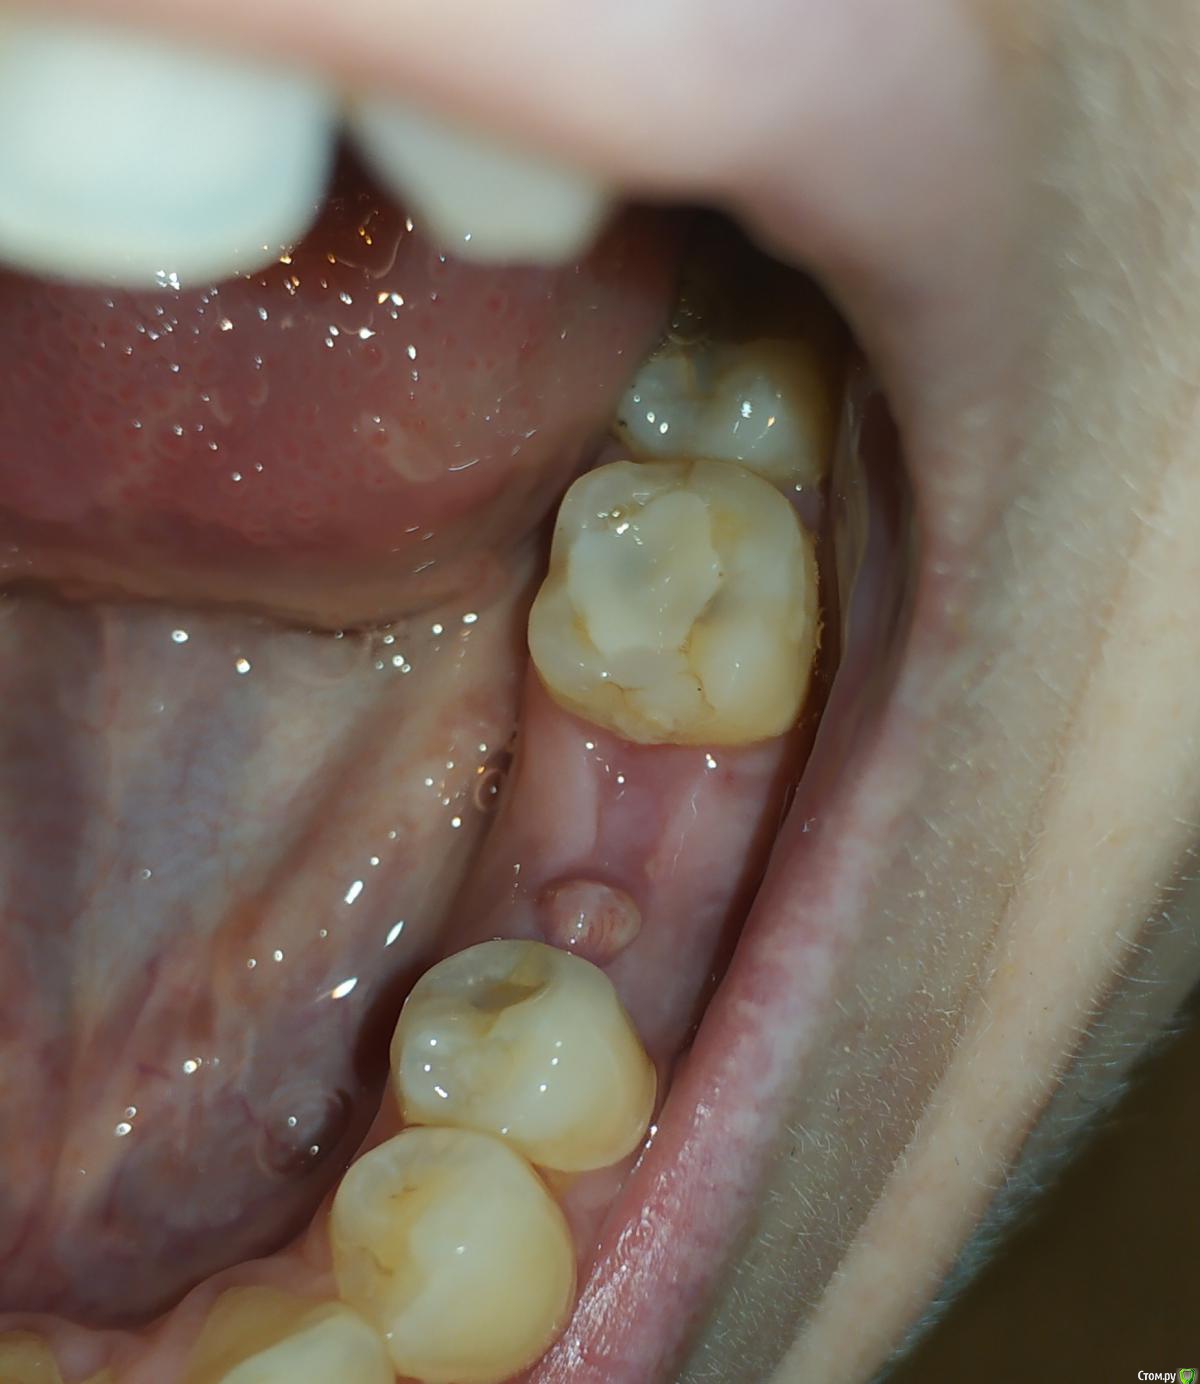

Jammy Опубликовано 22 октября, 2019 Поделиться Опубликовано 22 октября, 2019 (изменено) Доброго времени суток! 11 сентября удалили зуб, лунка заживала хорошо до недавнего времени. Вчера обнаружила странное образование в части лунки, чуть отличающееся по цвету от остальной десны.Выслала фото стоматологу, который удалял зуб, он сказал чтобы я не волновалась-это складка слизистой. Сегодня на этой складке появилось подкожное кровяное пятно. Стоит ли обращаться к врачу или это норма? Не сталкивалась ранее с процесс ом заживление лунки, оттого волнуюсь.Прошу прощения за качество фото (снимки сделаны вчера и сегодня) спасибо Изменено 22 октября, 2019 пользователем Jammy Ссылка на комментарий

dentikl Опубликовано 23 октября, 2019 Поделиться Опубликовано 23 октября, 2019 Доброго времени суток! 11 сентября удалили зуб, лунка заживала хорошо до недавнего времени. Вчера обнаружила странное образование в части лунки, чуть отличающееся по цвету от остальной десны.Выслала фото стоматологу, который удалял зуб, он сказал чтобы я не волновалась-это складка слизистой. Сегодня на этой складке появилось подкожное кровяное пятно. Стоит ли обращаться к врачу или это норма? Не сталкивалась ранее с процесс ом заживление лунки, оттого волнуюсь.Прошу прощения за качество фото (снимки сделаны вчера и сегодня) спасибопокажитесь 1 Ссылка на комментарий

dentikl Опубликовано 24 октября, 2019 Поделиться Опубликовано 24 октября, 2019 Спасибо за совет! сходила к стоматологу - терапевту, но мне сказали, что нужно записываться к стоматологу - хирургу..на снимок отправили- ничего на нем не обнаружено. У хирурга ещё не была, но терапевт упомянула слово грануляция и сказала, возможно потребуется чистка.да, было видно на Вашем фото Ссылка на комментарий